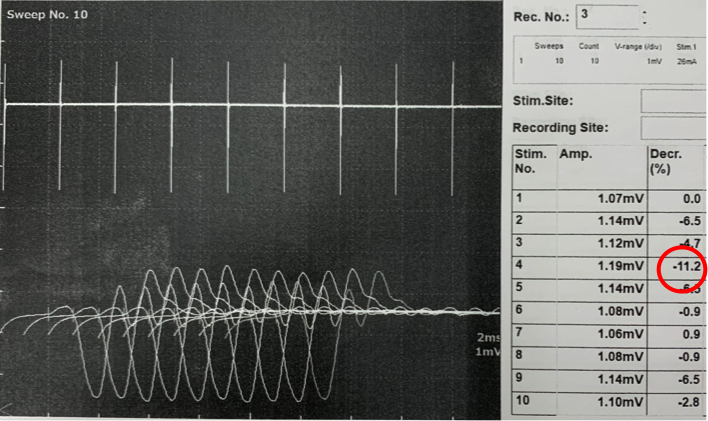

脛骨神経に2秒間隔で10回刺激を加えて、対応する筋肉の活動電位の変化をみる検査を実施しました。

重症筋無力症では4-5発目の刺激で活動電位の10%以上の低下を生じることが知られています。写真は実際の検査時の記録です。

2枚目の写真ではテンシロンを投薬した後の同様の検査となります。

投薬後の減少率は改善しており、効果が確認されました。薬の効果が切れた頃に再度実施すると減少率は10%以上を示していました。